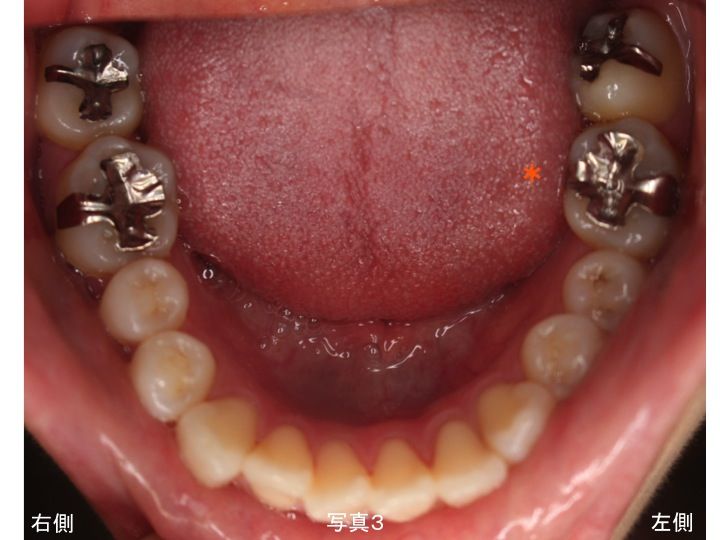

上下顎 左右側 ともに 多くの歯で金属製の詰め物や被せ物が装着してあります。

奥歯のみが噛み合っており、上下顎の前歯が噛み合っていないオープンバイトという状態です。

上顎右側の奥から4番目の歯は、白い状態に見えますが、これは仮歯のままです。

まず下顎です。

小さい金属製の詰め物は、コンポジットレジン(CR)●印

次に上顎です。

オープンバイト(前歯は噛み合ずに奥歯のみが噛み合っている)のため、

強度を重要視して金属部分撤去後は、

全てオールセラミック治療を行う計画を立てました。

●印はオールセラミックの部分的な詰め物、

●印は全体的に被せるオールセラミックです。

以下は、治療後の上下顎の写真です。